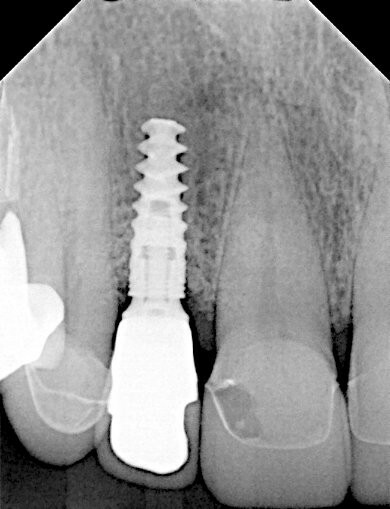

Wir behandelten in unserer Praxis einen Patienten, der über Schmerzen klagte, die durch eine Abszessbildung in Implantatregion 12 verursacht wurden. Das Implantat war ein Jahr zuvor von seinem Allgemeinzahnarzt inseriert worden.

Klinisch und radiologisch zeigte sich eine Entzündung mit Schwellung des Weichgewebes und Pusabsonderung auf Druck. Die Taschentiefe betrug 5-6 mm, der periimplantäre Knochenverlust betrug 3 mm.